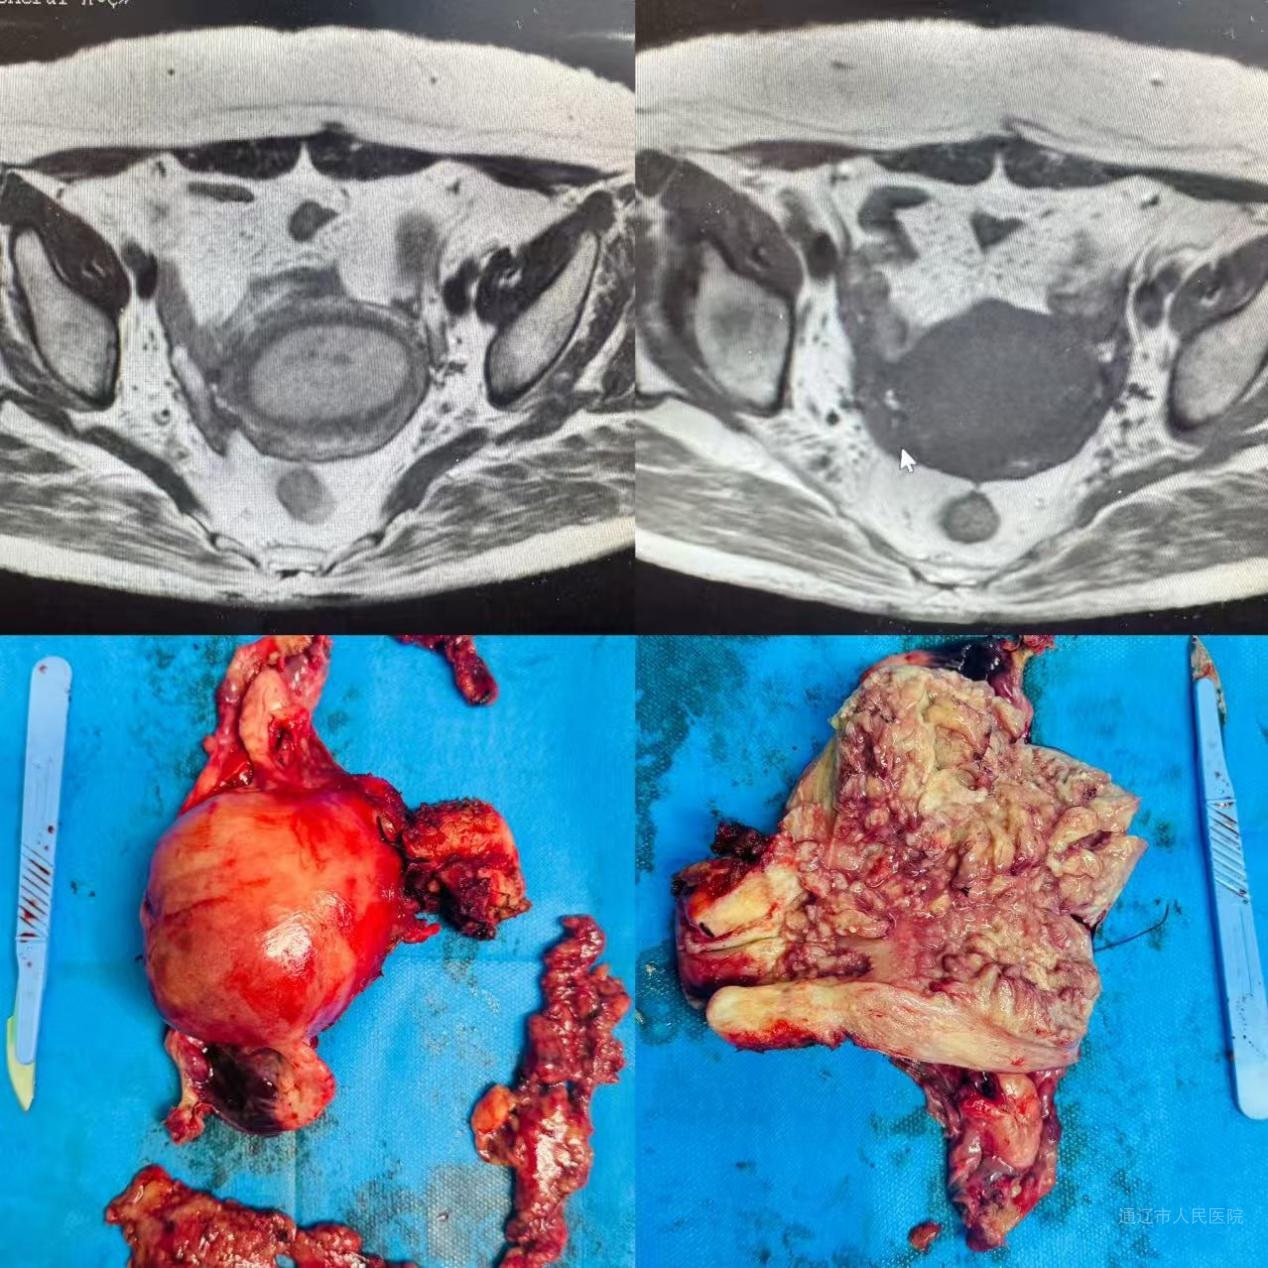

62岁的杨某某因绝经后阴道流血2年余就医,经超声检查及病理活检,确诊为子宫内膜样腺癌。术前评估显示肿瘤局限宫体但可能深肌层浸润。经妇科肿瘤MDT多学科会诊(妇科、影像科、病理科协同),为患者量身定制“腹腔镜下全子宫+双侧附件切除术+盆腔淋巴结清扫术+腹主动脉旁淋巴结清扫术”治疗方案。

手术由副主任医师白鹏来主刀,在麻醉科、护理团队配合下历时6小时顺利完成。术中运用三大关键技术:腹腔镜下全面探查,精准评估盆腹腔脏器及淋巴结转移情况;在肠系膜下动脉水平完成淋巴结清扫,精准切除双侧盆腔淋巴结及高位腹主动脉旁淋巴结,实现“零误伤”;经阴道完整取出病灶,环扎宫颈,防止肿瘤组织外溢,实现无瘤原则。针对高位淋巴清扫解剖复杂、肥胖患者术野暴露难、完整取出全子宫等技术难点,手术团队通过改良体位、精细操作能量器械等策略逐一攻克。

术后病理确诊为FIGO II期,为后续靶向治疗、放疗提供关键依据。高位淋巴结清扫显著降低复发风险,预计5年生存率提升至85%以上。凭借微创优势,患者术后次日即可下床活动。此次腹主动脉旁淋巴结清扫技术不仅填补区域技术空白,更体现多学科协作(MDT)在疑难肿瘤救治中的显著成效,为子宫内膜癌规范化诊疗提供重要实践样本,同时呼吁公众重视异常子宫出血等早期预警信号,及时就医诊治。